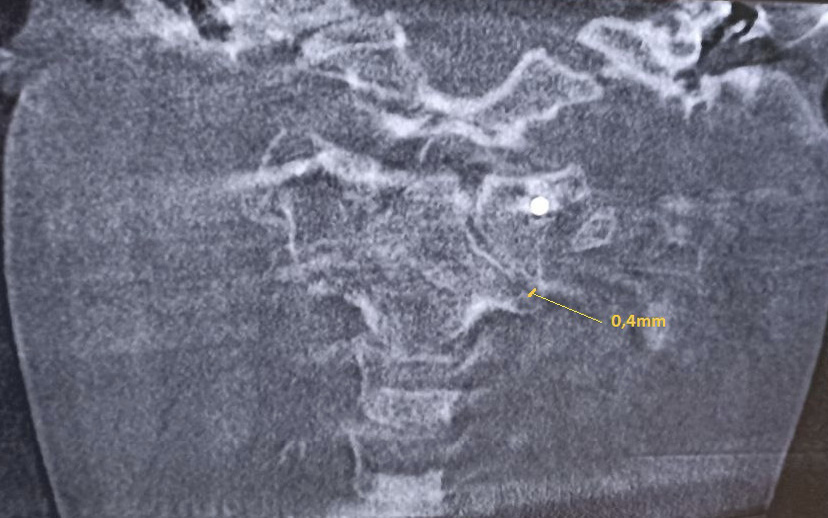

Клиническое наблюдение 1

Рис. 1. Конусно-лучевая компьютерная томография краниовертебральной области, фронтальный срез на уровне зубовидного отростка С2 позвонка. Методика измерения соотношений в латеральных атланто-аксиальных суставах